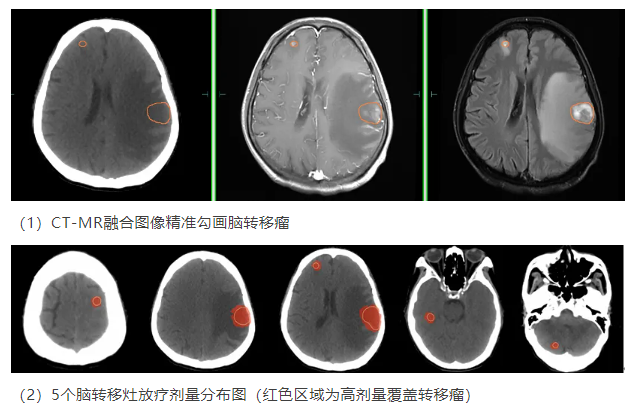

面对这一棘手难题,妇科肿瘤多学科诊疗(MDT)团队迅速行动,为王女士制定了综合治疗方案。在原有治疗的基础上,增加脑转移癌立体定向放疗。肿瘤六科陈意标主任医师团队凭借精湛的技术,通过CT-MR融合图像准确勾画出所有脑转移病灶,并于今年年初进行立体定向放疗。2个月后复查MR显示,5个转移灶有4个完全消失,最大的左侧颞顶交界转移瘤也明显缩小,大小从原来的2.6cm×1.7cm×2.7cm缩小至1.6cm×0.8cm×1.0cm,邻近脑实质受压移位较之前大幅改善,王女士的颅内高压症状逐步缓解,生活质量提升。